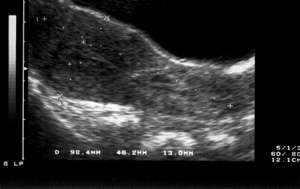

Εικόνα 3: Κύημα στο κατώτερο τμήμα της μήτρας Εικόνα 4: Αυξημένη διάταση μητριαίων αγγείων.

Η ασθενής αντιμετωπίζεται ως επαπειλούμενη αυτόματη αποβολή και εισάγεται για παρακολούθηση. Ο εργαστηριακός της έλεγχος είχε ως εξής: Ht 30, 1%, Hb 9, 6, WBC 11200, PLT 238000, APTT 28.7, χρόνος προθρομβίνης ασθ. 11.2-μαρτ.11.2, 100%, INR 1, 0, Ινωδογόνο 465, ουρία 28, σάκχαρο 87, κρεατινίνη 0, 7, ουρικό οξύ 3, 1, γGT 25, SGOT 31, SGPT 18, Na 139, K 3, 9, Γεν. ούρων 3-5 πυοσφαίρια κ.ο.π., 25-30 ερυθρά κ.ο.π., λοιπά κ.φ. Ακολουθεί σειρά υπερηχογραφημάτων και μετά πενθήμερου κατά τη διενέργεια κοιλιακού υπερηχογραφήματος, ανευρίσκεται εγκύμων μήτρα κενή περιεχομένου στον άνω πόλο με το κύημα στο κατώτερο τμήμα της. Τίθεται η υποψία έκτοπης κύησης (εικ. 3).